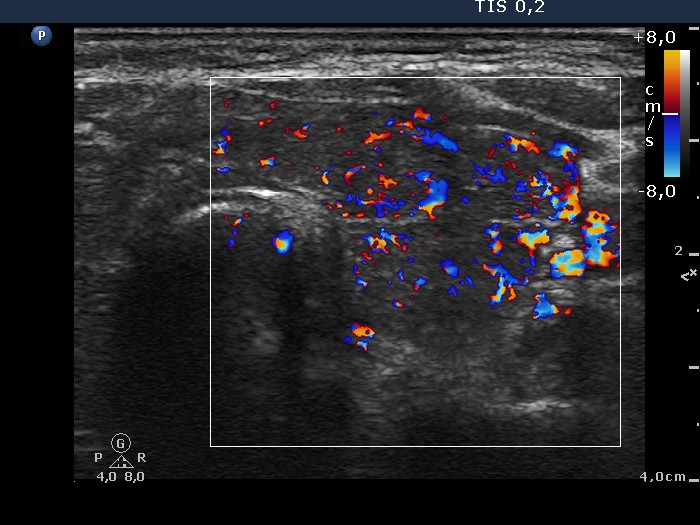

Graves' disease - case 612

Six weeks after the first visit (ultrasonographic picture 6)

Right lobe, transverse scan, color Doppler mode. The vascularization has been already increased but to a much lower extent than at the first exam.